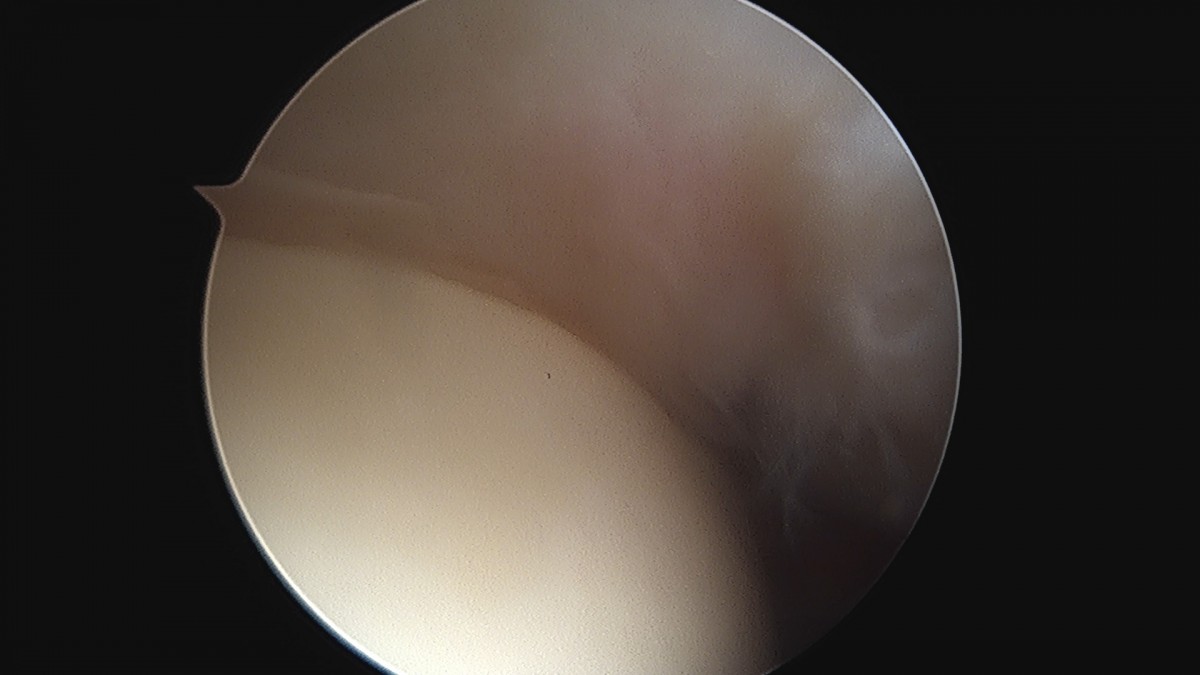

이재상원장님 어깨 견봉하 감압술 김봉O 환자

dae765e4d9ac96aee867c9d6292d8784_1758004118_8153.jpg